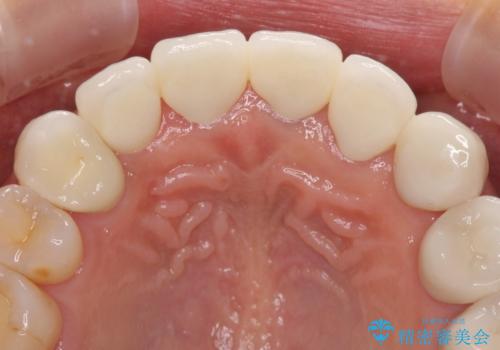

歯肉の高さをそろえたい 前歯の審美歯科治療

- 前歯の歯肉の高さが左右で異なっていることを気にして来院された患者様です。

歯肉レベルを調整するために歯周外科処置をおこない、その後にオールセラミッククラウンにて補綴することとしました。